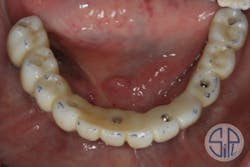

The fractured zirconia restoration was sectioned into two pieces, sandblasted, and then reseated as separate pieces. A new impression coping was placed on transmucosal abutment No. 27 (figure 7). All three pieces were luted together with resin as a new abutment level "pickup" impression (figure 8).

Figure 7: New impression coping placed on transucosal abutment No. 27

Figure 8: New abutment level "pickup" impression, with all three pieces luted together

The lab poured up a new model and milled a new zirconia restoration, which was delivered (whole this time!) with ease (figure 9).

Figure 9: New final laboratory-fabricated zirconia restoration based on abutment level "pickup" impression